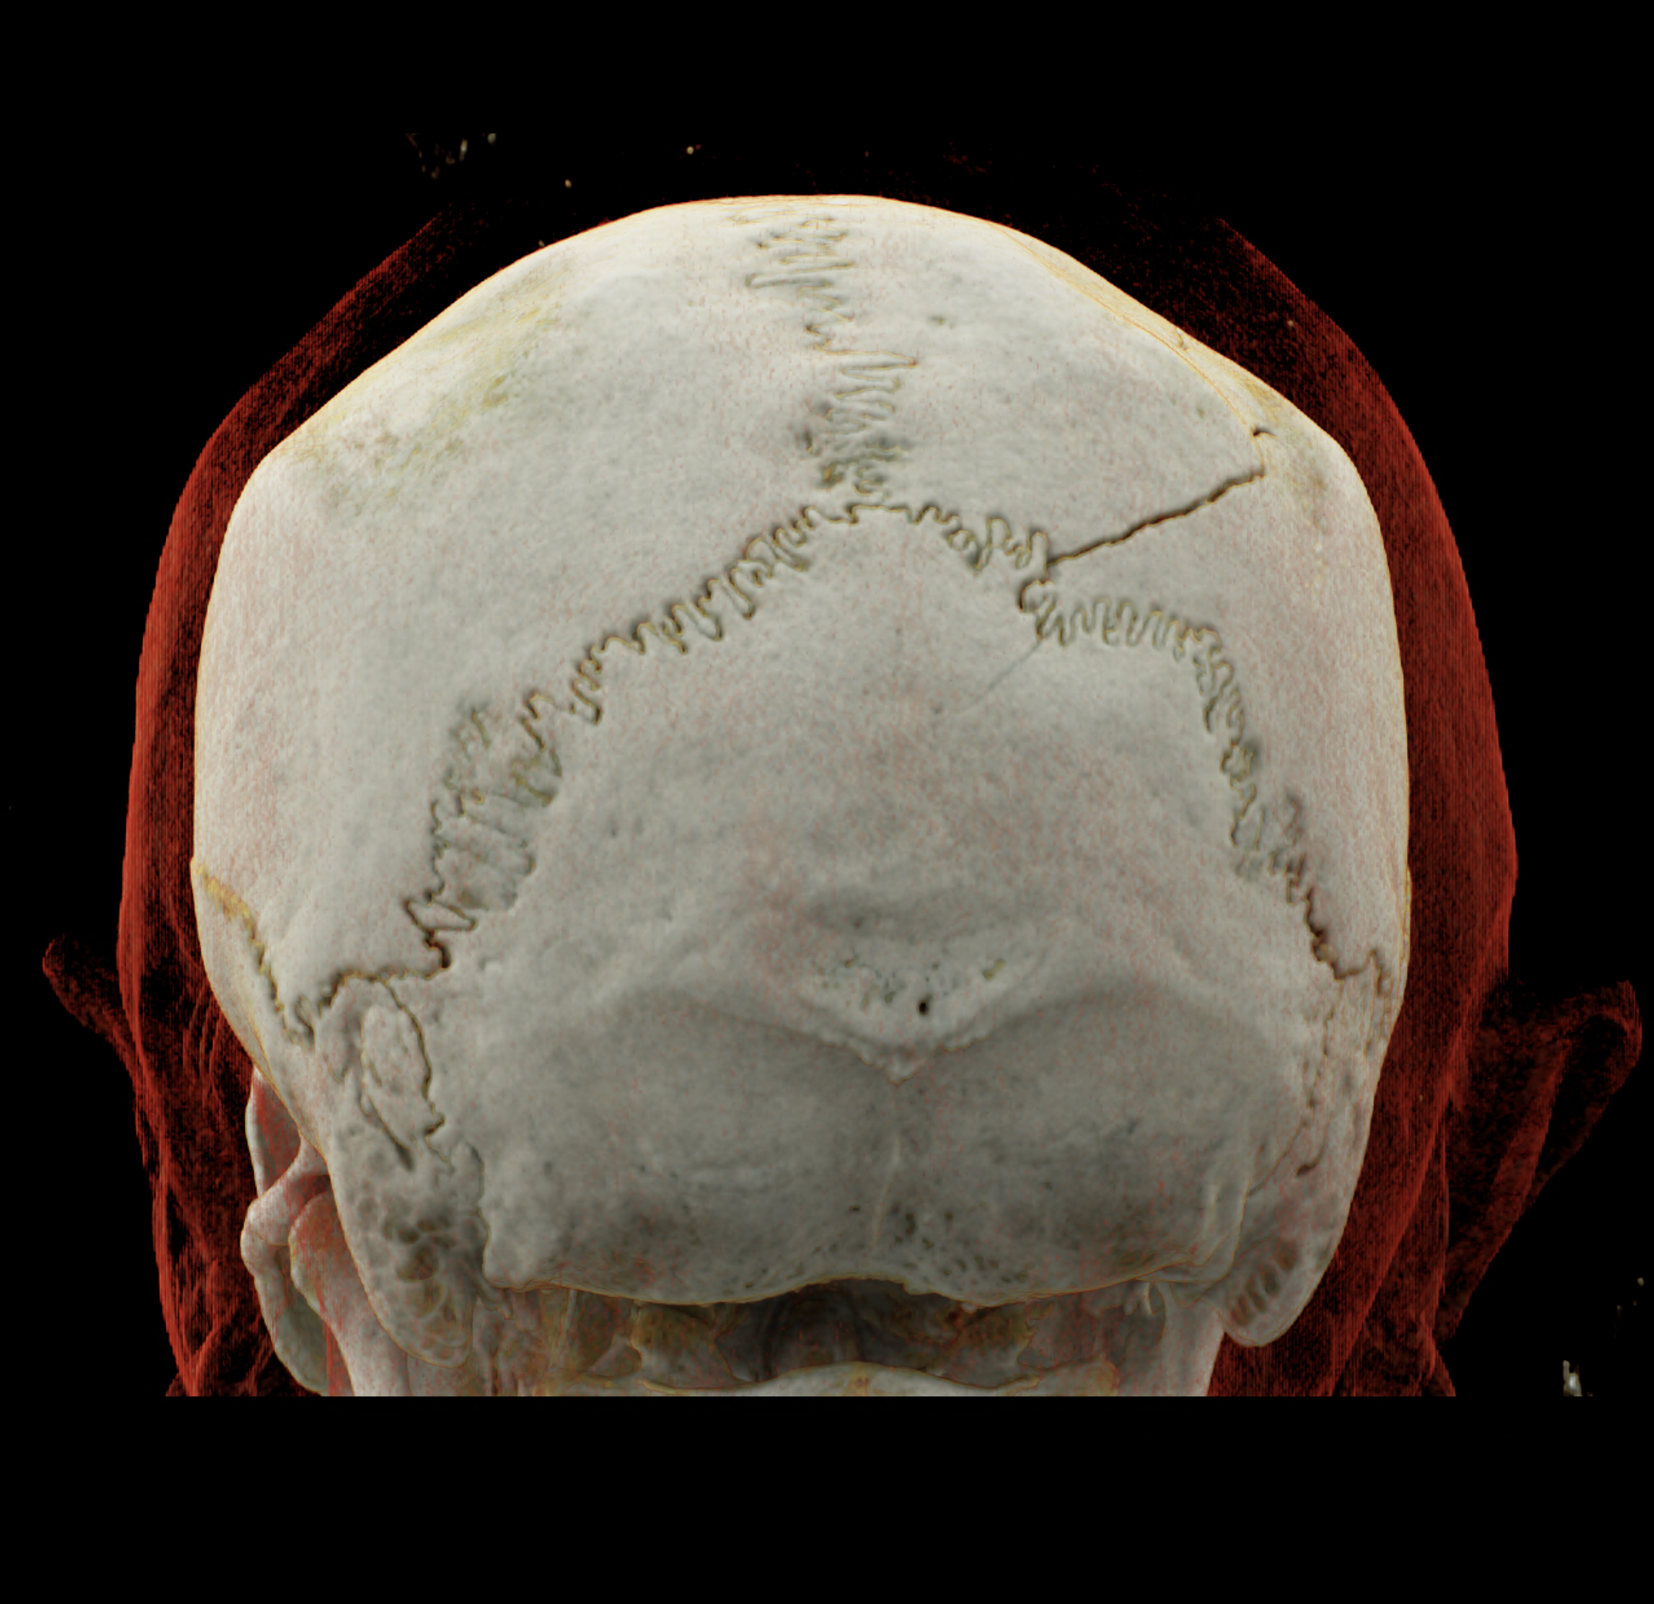

Three-dimensional reconstructions also show a complex skull fissure that extends from the frontal bone to the parietal and temporal bones.

volume rendered technique – display of the fissure course